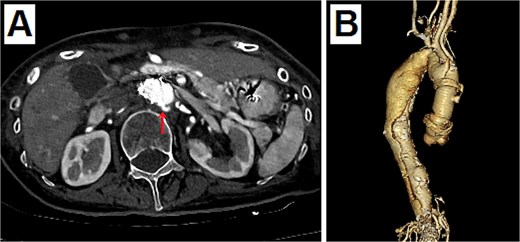

An 80-year-old woman presented with a progressively enlarging intrarenal AAA, measuring up to 50 mm. The patient’s performance status was relatively low; therefore, EVAR was selected to treat the AAA instead of open surgery. EVAR was performed under local anesthesia, and the procedure was conducted as usual (Gore Excluder 23 mm × 14.5 mm × 12 cm; W. L. Gore & Associates, Inc.; Delaware, USA). Ballooning was performed after implanting the main body stent graft and iliac limb extension stent graft. Subsequently, aortography was performed, which showed a type 1a endoleak. Therefore, ballooning was added at the top of the main body stent graft; however, the endoleak persisted. Thus, an additional stent graft (Gore Excluder 23 mm × 4.5 cm) was implanted at the upper end of the main body stent graft. Aortography was performed after ballooning; however, the flow was stagnating in the stent graft. At the same time, the pulse rate of the patient decreased suddenly, and she lost consciousness. She had pulseless electrical activity. Cardiopulmonary resuscitation was initiated, and an aortography was performed again. The presence of an aortic dissection was unclear; however, massive pericardial effusion was confirmed (Fig. 1). Cardiac tamponade by RTAD was suspected, and median sternotomy was performed emergently. After pericardiotomy, the pericardial cavity was filled with blood and hematoma, and spontaneous pulse returned after their removal. However, the adventitia of the aortic root was ruptured, and bleeding persisted. Therefore, ascending aortic replacement or aortic root replacement was performed. Cardiopulmonary bypass was established via left femoral artery perfusion and bicaval drainage. After the nasopharyngeal temperature reached 22°C, circulatory arrest was initiated. The ascending aorta was incised, and the lumen was checked. No tear was found at the intima of the ascending aorta and aortic root. Therefore, ascending aortic replacement was performed (Triplex Advanced 26 mm, Vascutek Terumo, Tokyo, Japan) with retrograde cerebral perfusion. The operation was completed without incident. The patient was extubated on the first postoperative day, and the postoperative course was uneventful. The postoperative enhanced computed tomography (CT) revealed that the entry of the dissection existed at the top of the stent at the abdominal aorta, and the dissection was connected to the distal side of the ascending aortic artificial graft (Fig. 2). The patient was discharged 30 days postoperatively. At the 1-year follow-up, the aorta treated for dissection remained stable.

Postoperative enhanced CT. (A) The entry of dissection existed at the top of the stent at the abdominal aorta (arrow). (B) The 3D CT viewed from the right side. The dissection was connected to the distal side of the ascending aortic artificial graft from the top of the stent at the abdominal aorta.